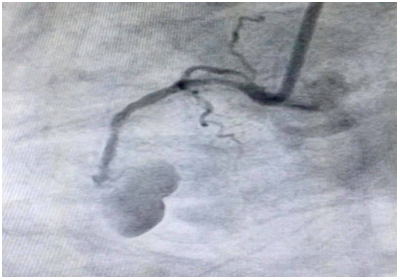

On Echocardiogram Mild RWMA seen with LVEF 42%, other parameters were in normal range. Coronary Angiogram revealed a focal stenosis in the proximal RCA and Pseudoanurysm was seen in RCA (Previously stented).

The patient was having recurrent chest pain 2 month after the initial percutaneous coronary intervention (PCI), and he was taken for repeat coronary angiography on the day admission. The RCA stent was occluded. However, just outside of the mid-portion of the stent was collection of contrast, which appeared to reveal a pseudoaneurysm.

Figure 1 Pseudoaneurysm in RCA (CAG).

The prevalence of coronary-artery pseudoaneurysms in cases undergoing coronary angiography is reportedly 0.2–10%. Such pseudoaneurysms occurred in the right coronary artery, left anterior descending branch, left circumflex branch, and left main trunk in 40.4%, 32.3%, 23.4%, and 3.5%, respectively, of all cases. Most cases are asymptomatic.5 Coronary-artery pseudoaneurysms can have a wide variety of causes. The present case is believed to be iatrogenic because the RCA readily experienced vascular-wall damage from catheters and guide wires. The morphology was saccular for this pseudoaneurysm. The pseudoaneurysm formed after PCI in July 2018, and the patient’s medical history did not include other diseases that could induce it. The incidence of iatrogenic coronary artery pseudoaneurysms during catheter examination or treatment is approximately 0.1%, and RCA lesions occur in approximately 0.07% of cases. It occurs more frequently with percutaneous coronary angioplasty, and twice as often with coronary angi-ography.6 Causes include anatomical anomalies in the coronary artery, atherosclerosis, rapidly injected contrast agent, catheter type (it is significantly more frequent with left Amplatz guiding catheters), improper catheter placement, and deep engagement during balloon drawing.7–10 Our case was a large pseudoaneurysm as observed in coronary angiogram, so we did surgical correction for it.